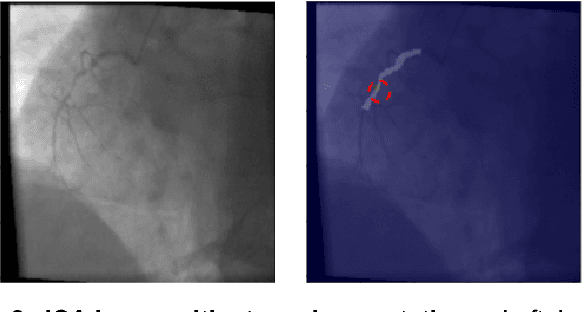

Abstract:The determination of a coronary stenosis and its severity in current clinical workflow is typically accomplished manually via physician visual assessment (PVA) during invasive coronary angiography. While PVA has shown large inter-rater variability, the more reliable and accurate alternative of Quantitative Coronary Angiography (QCA) is challenging to perform in real-time due to the busy workflow in cardiac catheterization laboratories. We propose a deep learning approach based on Convolutional Neural Networks (CNN) that automatically characterizes and analyzes coronary stenoses in real-time by automating clinical tasks performed during QCA. Our deep learning methods for localization, segmentation and classification of stenosis in still-frame invasive coronary angiography (ICA) images of the right coronary artery (RCA) achieve performance of 72.7% localization accuracy, 0.704 dice coefficient and 0.825 C-statistic in each respective task. Integrated in an end-to-end approach, our model's performance shows statistically significant improvement in false discovery rate over the current standard in real-time clinical stenosis assessment, PVA. To the best of the authors' knowledge, this is the first time an automated machine learning system has been developed that can implement tasks performed in QCA, and the first time an automated machine learning system has demonstrated significant improvement over the current clinical standard for rapid RCA stenosis analysis.